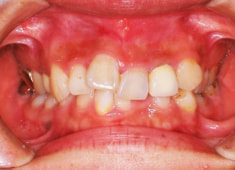

治療前